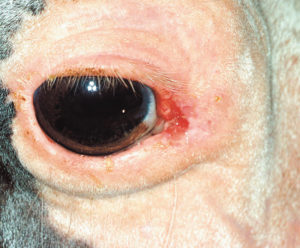

Protect Horses From Sun to Prevent SCC Recurrence

Researchers found that the only factor associated with a decreased risk of squamous cell carcinoma (or SCC, the most common ocular tumor in horses) recurrence was use of a fly mask with 90% or more UV light protection.